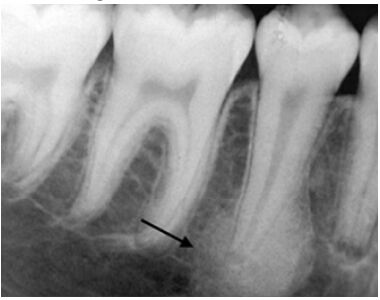

44.圖中箭頭所指的骨折,下列何者正確?①favorable fracture ②unfavorable fracture ③容易錯位 ④ 不容易錯位

(A)②④ (B)①③ (C)①④ (D)②③